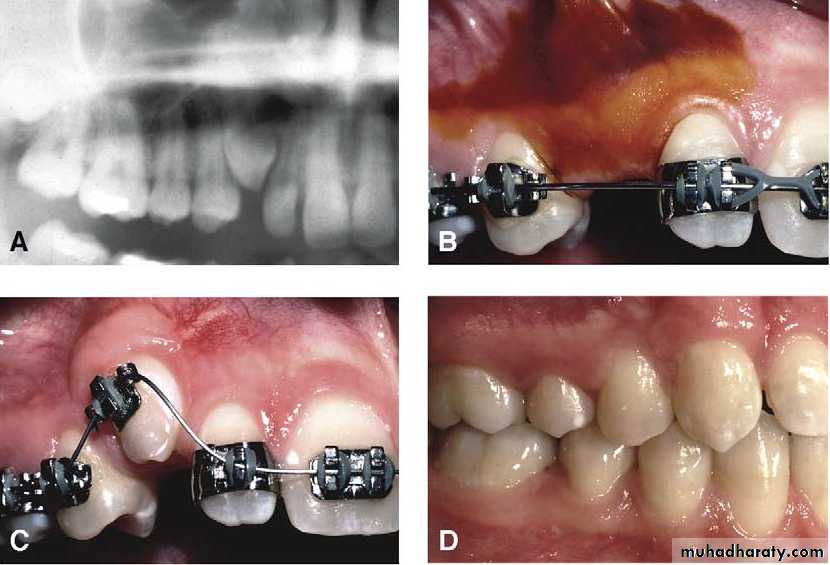

Surgical exposure

An attempt is made to assist the eruption of a malposed and unerupted canine into a functional position . It is considered when :1- there is adequate room in the arch to accommodate the tooth .

2- the potential path of eruption is unobstructed

3- exposure of the crown can be carried out as close as possible to the time at which normal eruption would occur .

Surgical exposure :the path of eruption is not obstructed

Surgical exposure with orthodontic traction: the path of eruption is obstructed

Surgical exposure with orthodontic treatment (palatal approach )

The initial stage of the operation is to reflect the mucoperiosteum and to remove the bone overlying the tooth to expose the greatest coronal diameter, the incisal edge and the cingulum . before repositioning the palatal flap a window is excised in it corresponding to the bony cavity containing the crown .the flap is then sutured as usual and a pack of iodoform gauze should be pressed firmly in to the bony defect so as to cover the exposed crown .

This pack should be held in position with suture and left insitu for 2-3 weeks to prevent granulation tissue and mucosa from overgrowing the denuded crown .after removal of the pack the progress of eruption should be observed at frequent intervals .

Following eruption of the tooth , orthodontic treatment may be required to guide it into a good position in the arch . Some times orthodontic traction is arranged at the time of surgery .